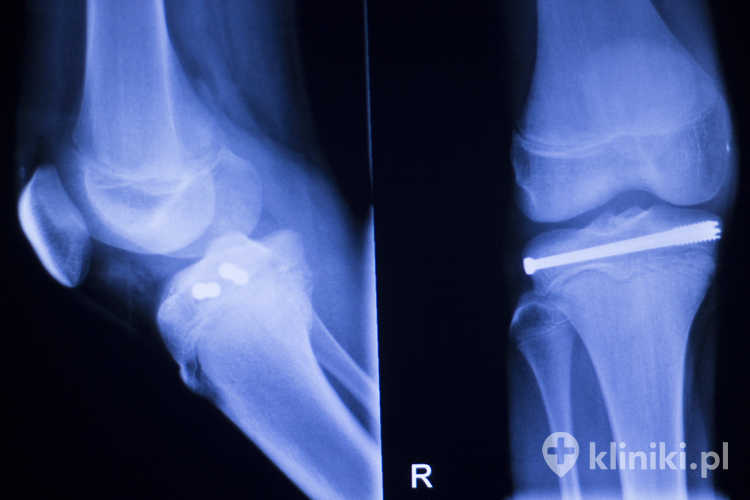

Zależnie od przeznaczenia i zakresu zabiegu implanty ortopedyczne przyjmują rozmaite formy, niekiedy o dość skomplikowanym kształcie. Mogą to być m.in. gwoździe kostne, gwoździe śródszpikowe blokowane, płytki kostne płaskie, kątowe lub kształtowe oraz śruby i wkręty kostne.

• Konieczność precyzyjnej, długotrwałej kontroli radiologicznej położenia śrub/płytek – część bioresorbowalnych elementów jest słabiej widoczna w RTG.